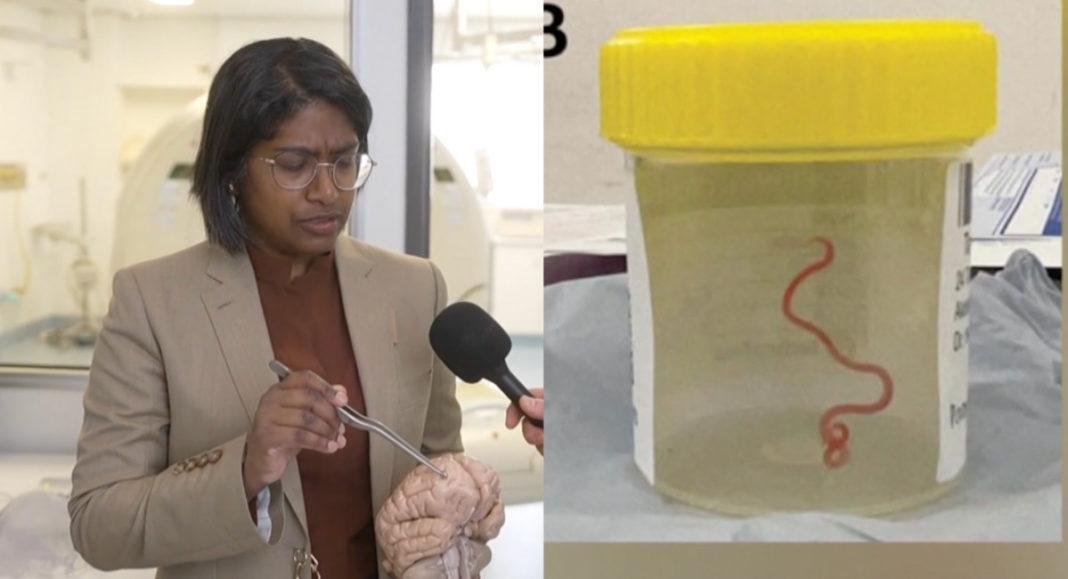

Indian Australian Neurosurgeon Dr Hari Priya Bandi shared her astonishment,

“I’ve only come across worms using my not-so-good gardening skills… I find them terrifying and this is not something I deal with at all.”

Dr. Bandi performed brain surgery on a 64-year-old woman and was taken aback when she pulled out an 8-centimetre (3-inch) long parasitic roundworm that was still wriggling between her forceps.

The parasite was identified as Ophidascaris Robertsi, a roundworm typically found in pythons, after a thorough examination and molecular tests.